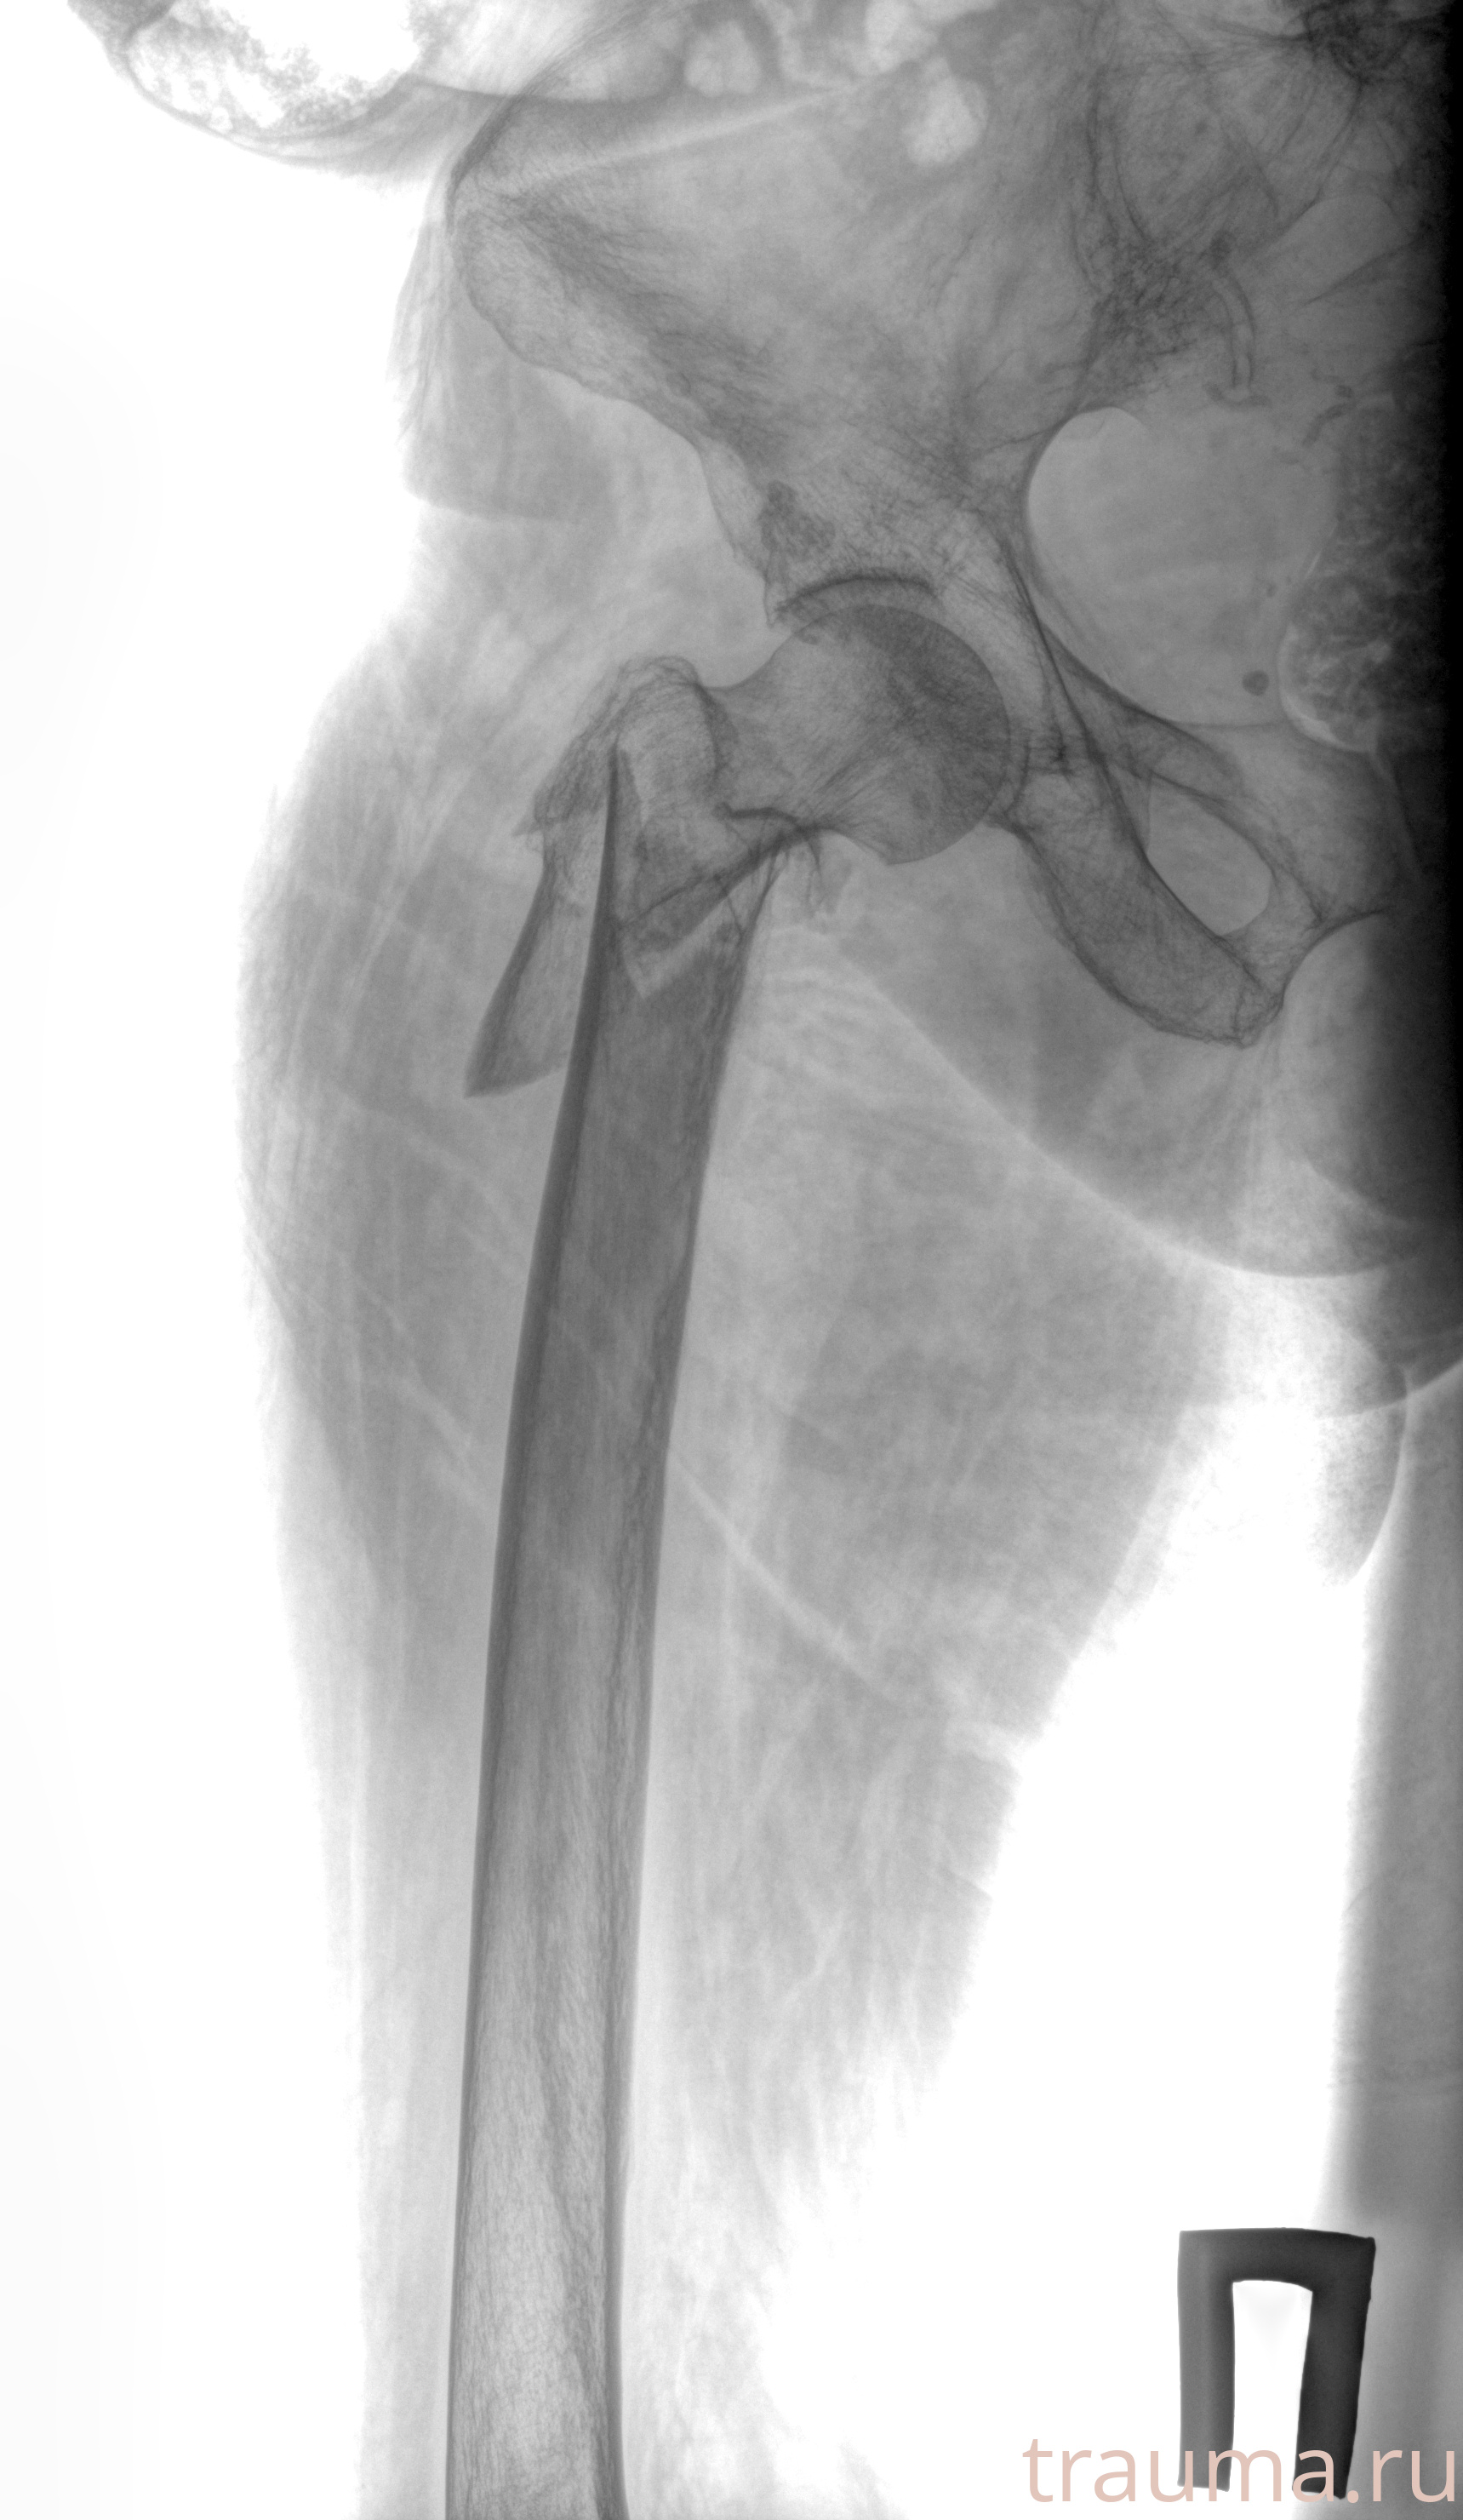

Рентгенограммы

Рентген на дому: по вашему адресу приезжает врач-рентгенолог, травматолог-ортопед с мобильным рентгеновским аппаратом, проводит диагностику травмы или заболевания, делает необходимые рентгенограммы, дает рекомендации по дальнейшему лечению. Получить качественные снимки в домашних условиях возможно благодаря уникальной методике, разработанной МосРентген Центром для института  Склифосовского